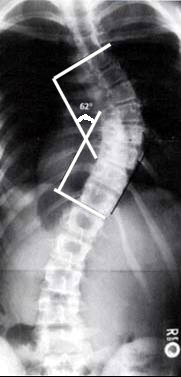

Spinal X-rays: Cobb method of determining angle of curvature

1. Choose the most tilted verterbrae above & below apex of the curve.

2. Angle between intersecting lines drawn perpendicular to the top of the superior vertebrae and bottom of the inferior vertebrae is the Cobb angle.

In general a Cobb angles greater than 10% is required to make a positive diagnosis and less than 10% is regarded as normal.

Diagram: Finding the Cobb angle. For precise description of how to determine the Cobb angle from an x-ray picture, go to spinalmedicine.com